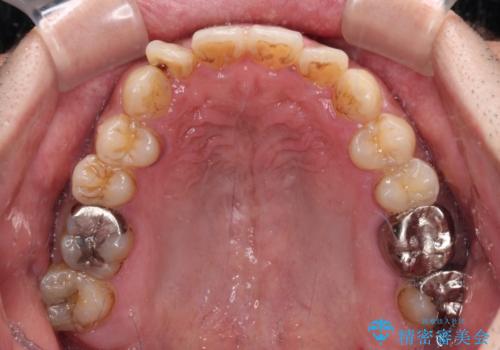

- 前歯のデコボコを気にして来院された患者様です。

前歯が90度近く捻れていたため、しっかりと治すことを考えるとワイヤー矯正の方がおすすめではありましたが、本人の希望によりインビザラインを用いて矯正治療を行うこととしました。

インビザラインは、十分な装着時間が達成されると前歯のデコボコをしっかりと改善できますが、1日の装着時間が20時間に達しなくなると、不十分な仕上がりとなるため、しっかりと装着するよう指示をしました。

途中2年強の来院がなく、改善されていたデコボコが元に戻ったり、装着時間が不足しており前歯のデコボコは十分に改善することはできませんでしたが、5年間の有効期限内で可能な限り歯列を整えることができました。